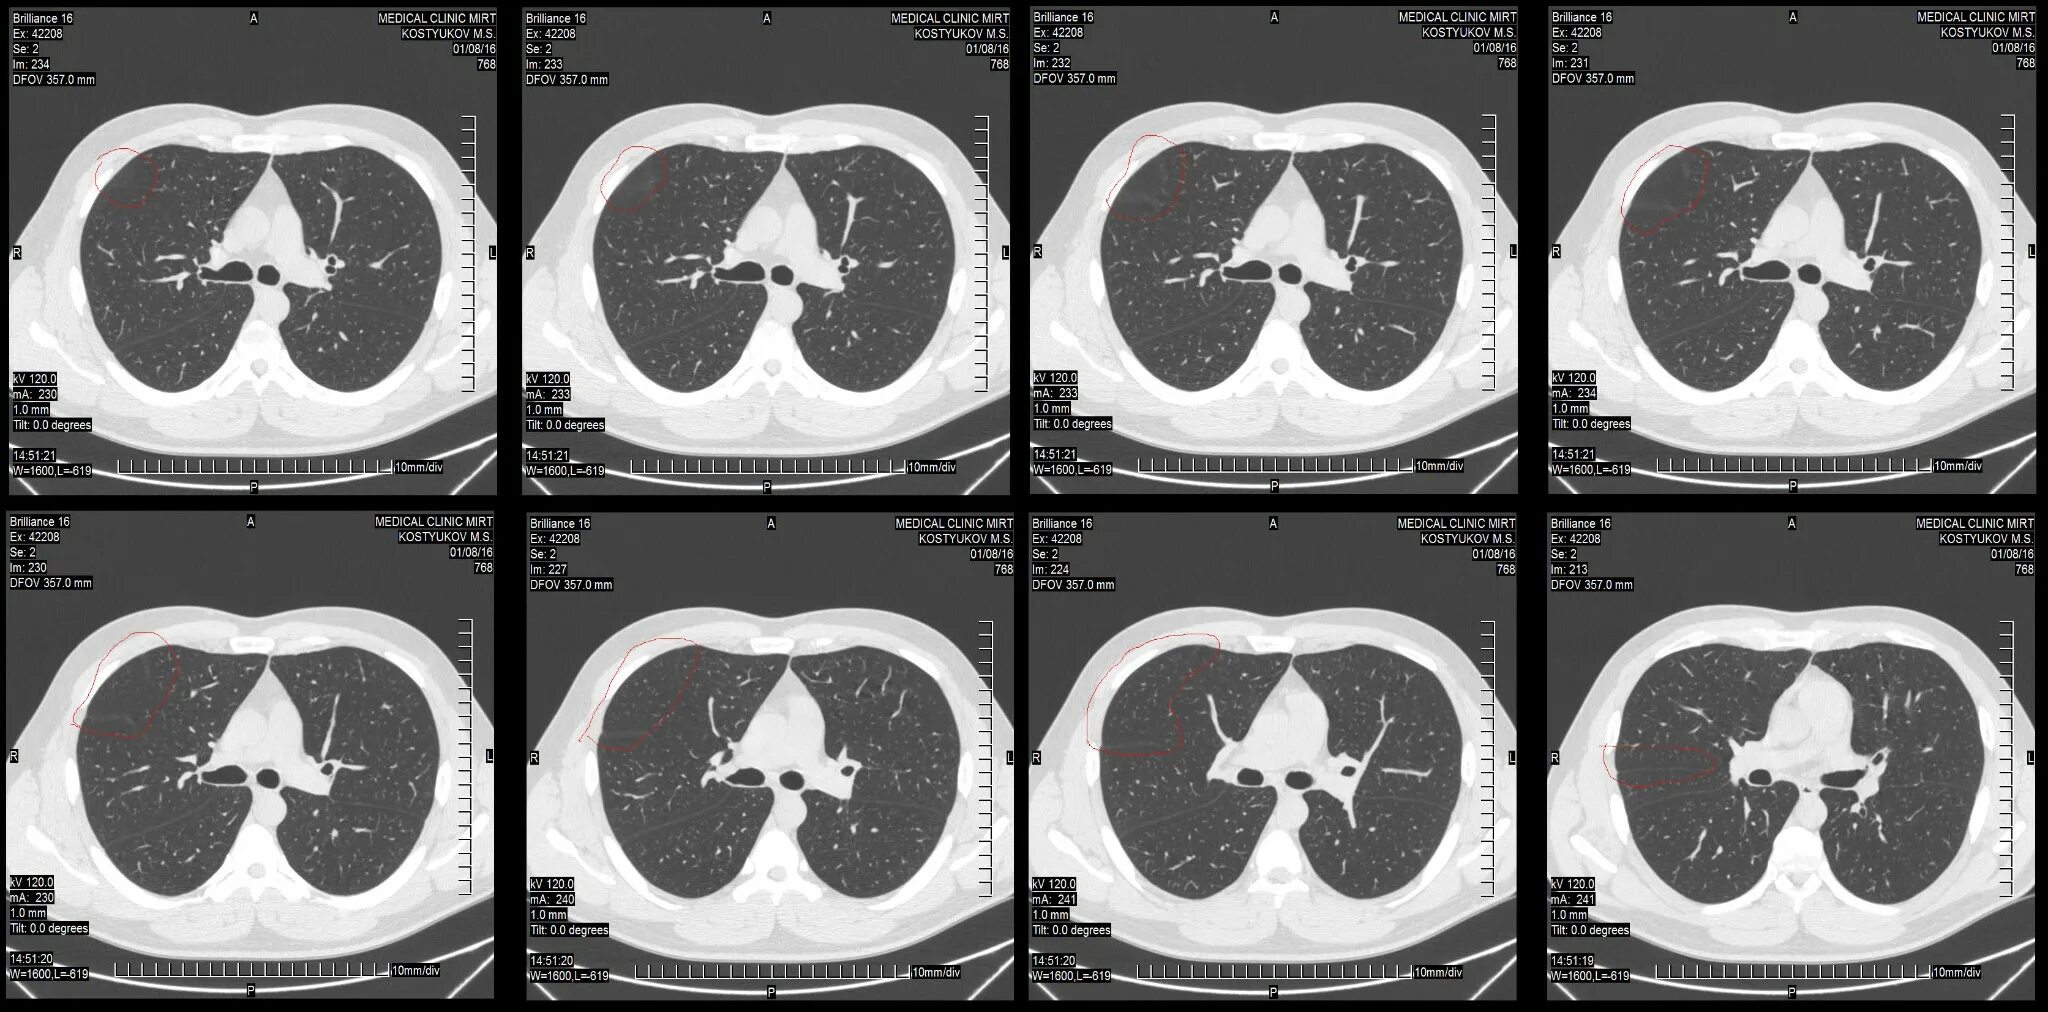

Какие виды кт